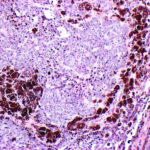

Pigmented Basal Cell Carcinoma

Pigmented BCC shows histologic features similar to those of nodular BCC but with the addition of melanin.38 Approximately 75 percent of BCCs contain melanocytes, but only 25 percent contain large amounts of melanin. The melanocytes are interspersed between tumor cells and contain numerous melanin granules in their cytoplasm and dendrites. Although the tumor cells contain little melanin, numerous melanophages populate the stroma surrounding the tumor.